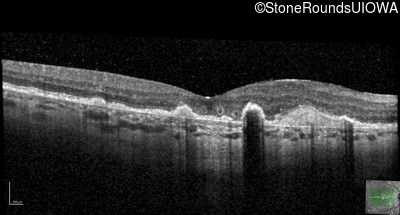

Malattia Leventinese (IIJ)

Malattia Leventinese (IIJ)

This 43 year old woman has experienced a gradual reduction in her central vision for the past 3 years.

| Malattia Leventinese | EFEMP1 | Arg345Trp CGG>TGG | AD |